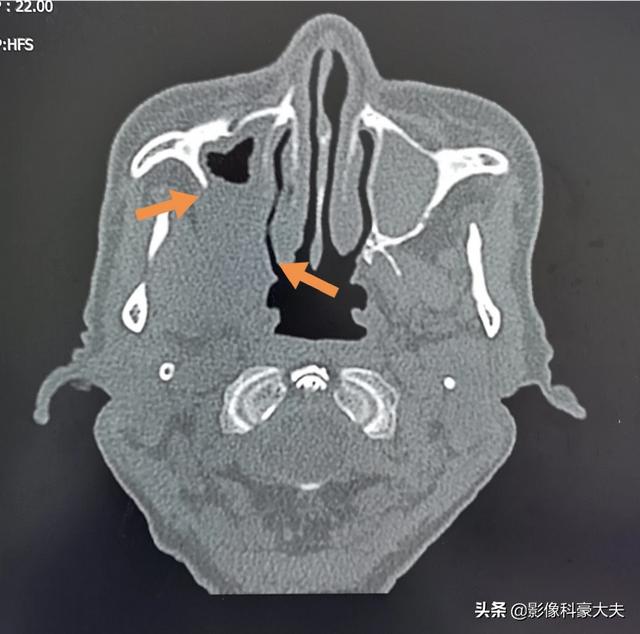

Dieser alte Mann mit Zahnschmerzen auf der rechten Seite und Schmerzen in der Wangenblase nimmt seit mehr als zwei Monaten Medikamente ein, als wäre er ein alter Mann mit einer Zahnwurzelentzündung, aber er istKnochenzerstörung bei KieferhöhlenkrebsAuf.

Welche Art von Schmerzen sollten auf eine Knochenmetastase hinweisen? Knochenmetastasen sind eine häufige Erscheinung bei bösartigen Tumoren im Spätstadium, d. h. der Primärtumor ist über Blut- und Lymphbahnen in andere Körperteile eingedrungen und hat dort Knochenmetastasen gebildet. Knochenmetastasen bedeuten, dass normales Knochengewebe zerstört und durch Tumorgewebe ersetzt worden ist. Knochenmetastasen lassen sich je nach Spezifität der Läsion in drei Typen einteilen: osteolytischer Typ, osteogener Typ und Mischtyp. Die häufigsten Stellen, an denen Knochenmetastasen auftreten, sind der mittlere Schaftknochen (Wirbelsäule und Becken), die Rippen und die untere Metaphyse, wobei vor allem der mittlere Schaftknochen am häufigsten betroffen ist, was mit den Eigenschaften der Blutversorgung in diesem Bereich zusammenhängt. Wie im Kreis unten dargestellt, gibt es mehrere Knochenmetastasen und die Wirbelsäule ist in einem schlechten Zustand.